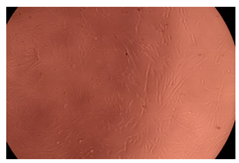

2.4. In Vitro Cytotoxicity Analysis

| Control |  |  | |

| Cop B | 10 µg/mL |  |  |

| 50 µg/mL |  |  | |

| 100 µg/mL |  |  | |

| Cop B/IMC = 10/1 (wt/wt) | 10 µg/mL |  |  |

| 50 µg/mL |  |  | |

| 100 µg/mL |  |  | |

| Cop B/Dorzolamide = 10/1 (wt/wt) | 10 µg/mL |  |  |

| 50 µg/mL |  |  | |

| 100 µg/mL |  |  | |